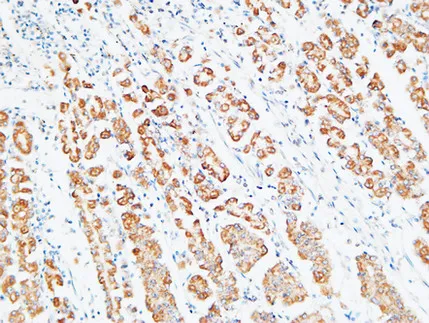

FEN-1 Rabbit Polyclonal Antibody

Cat: APRab10901

Size1:50μl Price1:$118

Size2:100μl Price2:$220

Size3:500μl Price3:$980